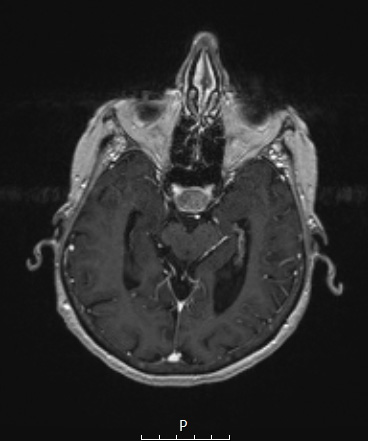

This T1-weighted suprasellar mass enhances heterogeneously